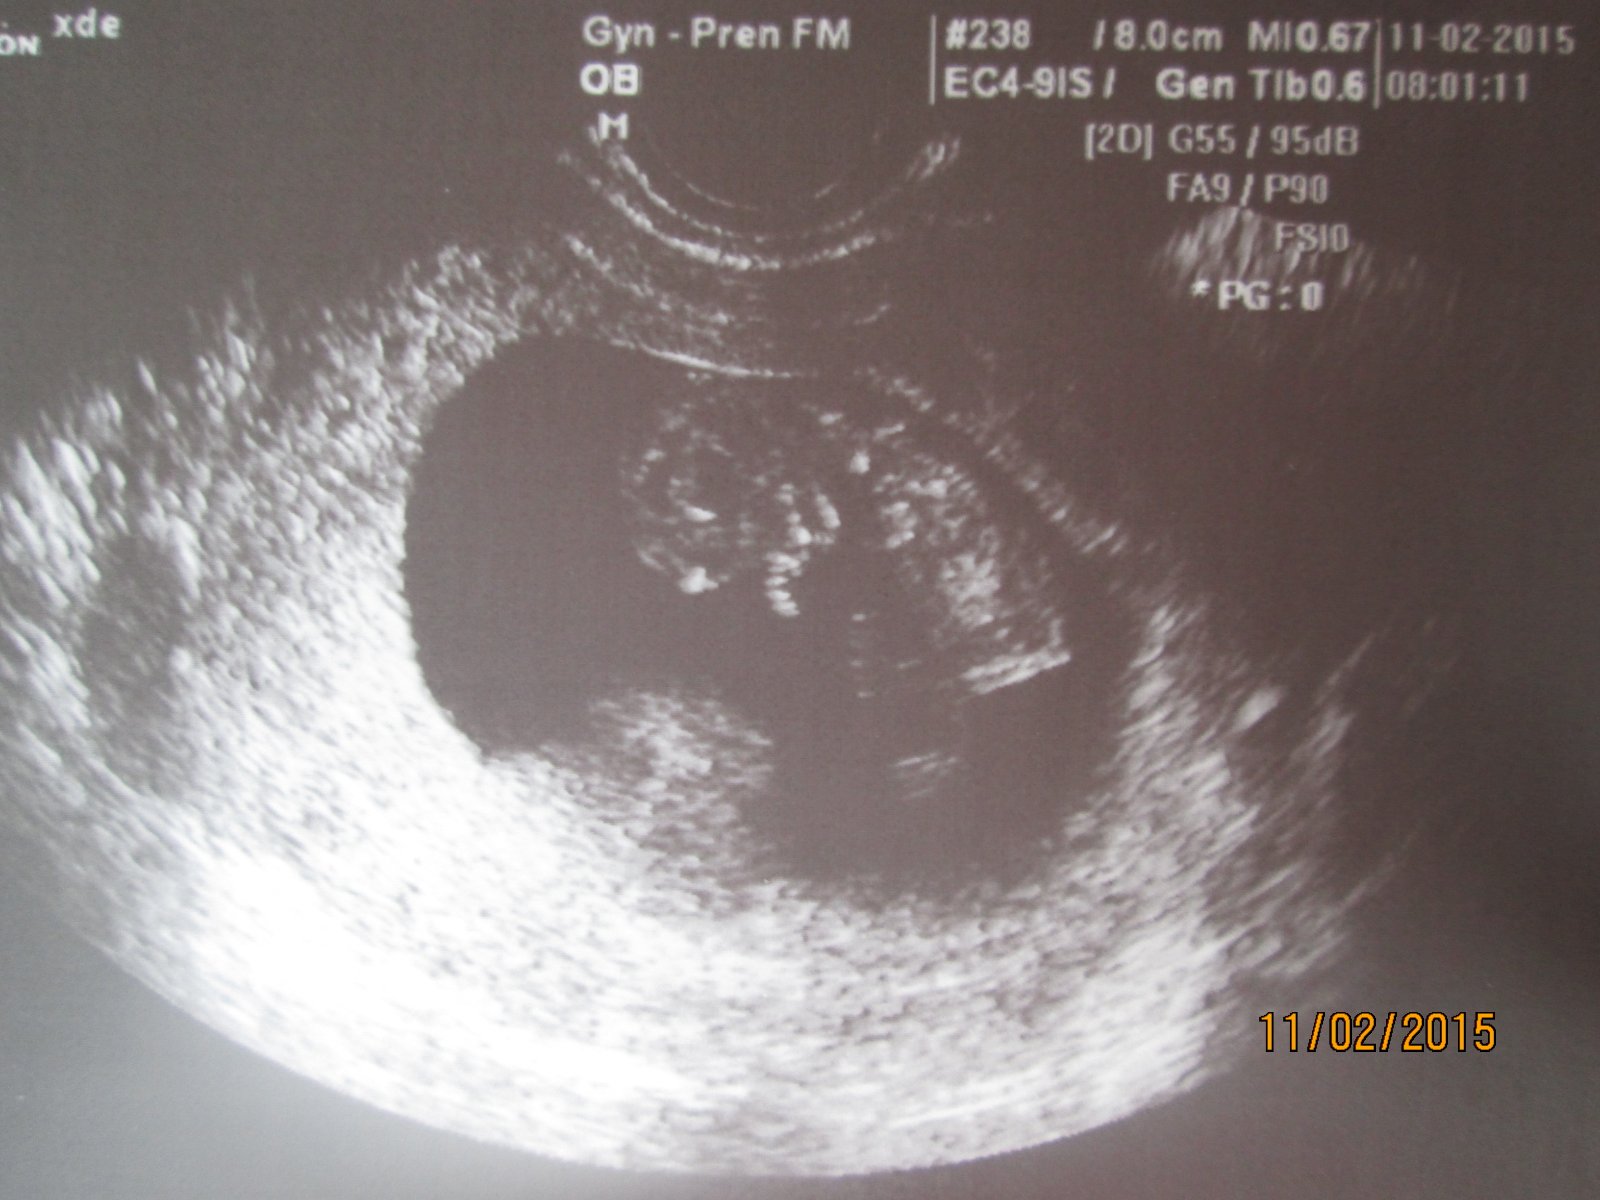

@nonacek Koukni na tuhle diskuzi je tam hezky vidět,jak má vypadat kávové zrno a pod tím je tam někde i chlapeček 🙂 Tak zkus porovnat a kdyby sis nevěděla rady,tak ti pak do soukromé zprávy napíšu můj email a můžeš zkusit poslat 🙂 https://www.modrykonik.cz/forum/2-trimestr/je-to-holcicka-nebo-chlapecek-foto-ultrazvuku/